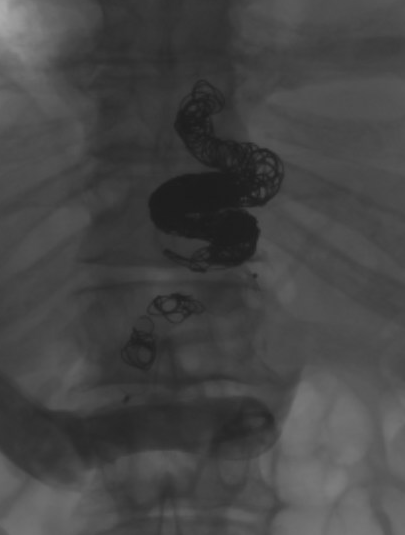

@UCD_IR

Jon Lindquist

3 years

Don't step on this coiled rattler. Large gastroesophageal varices can be fragile and bleed quickly! Antegrade coil and plug embolized-- does that make it a CATO/PATO? #irad @IrColorado

1

3

28